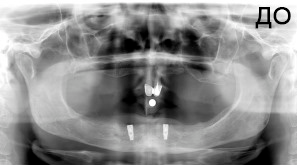

4 работы в портфолио

Акопян Антон Владимирович: портфолио (4)